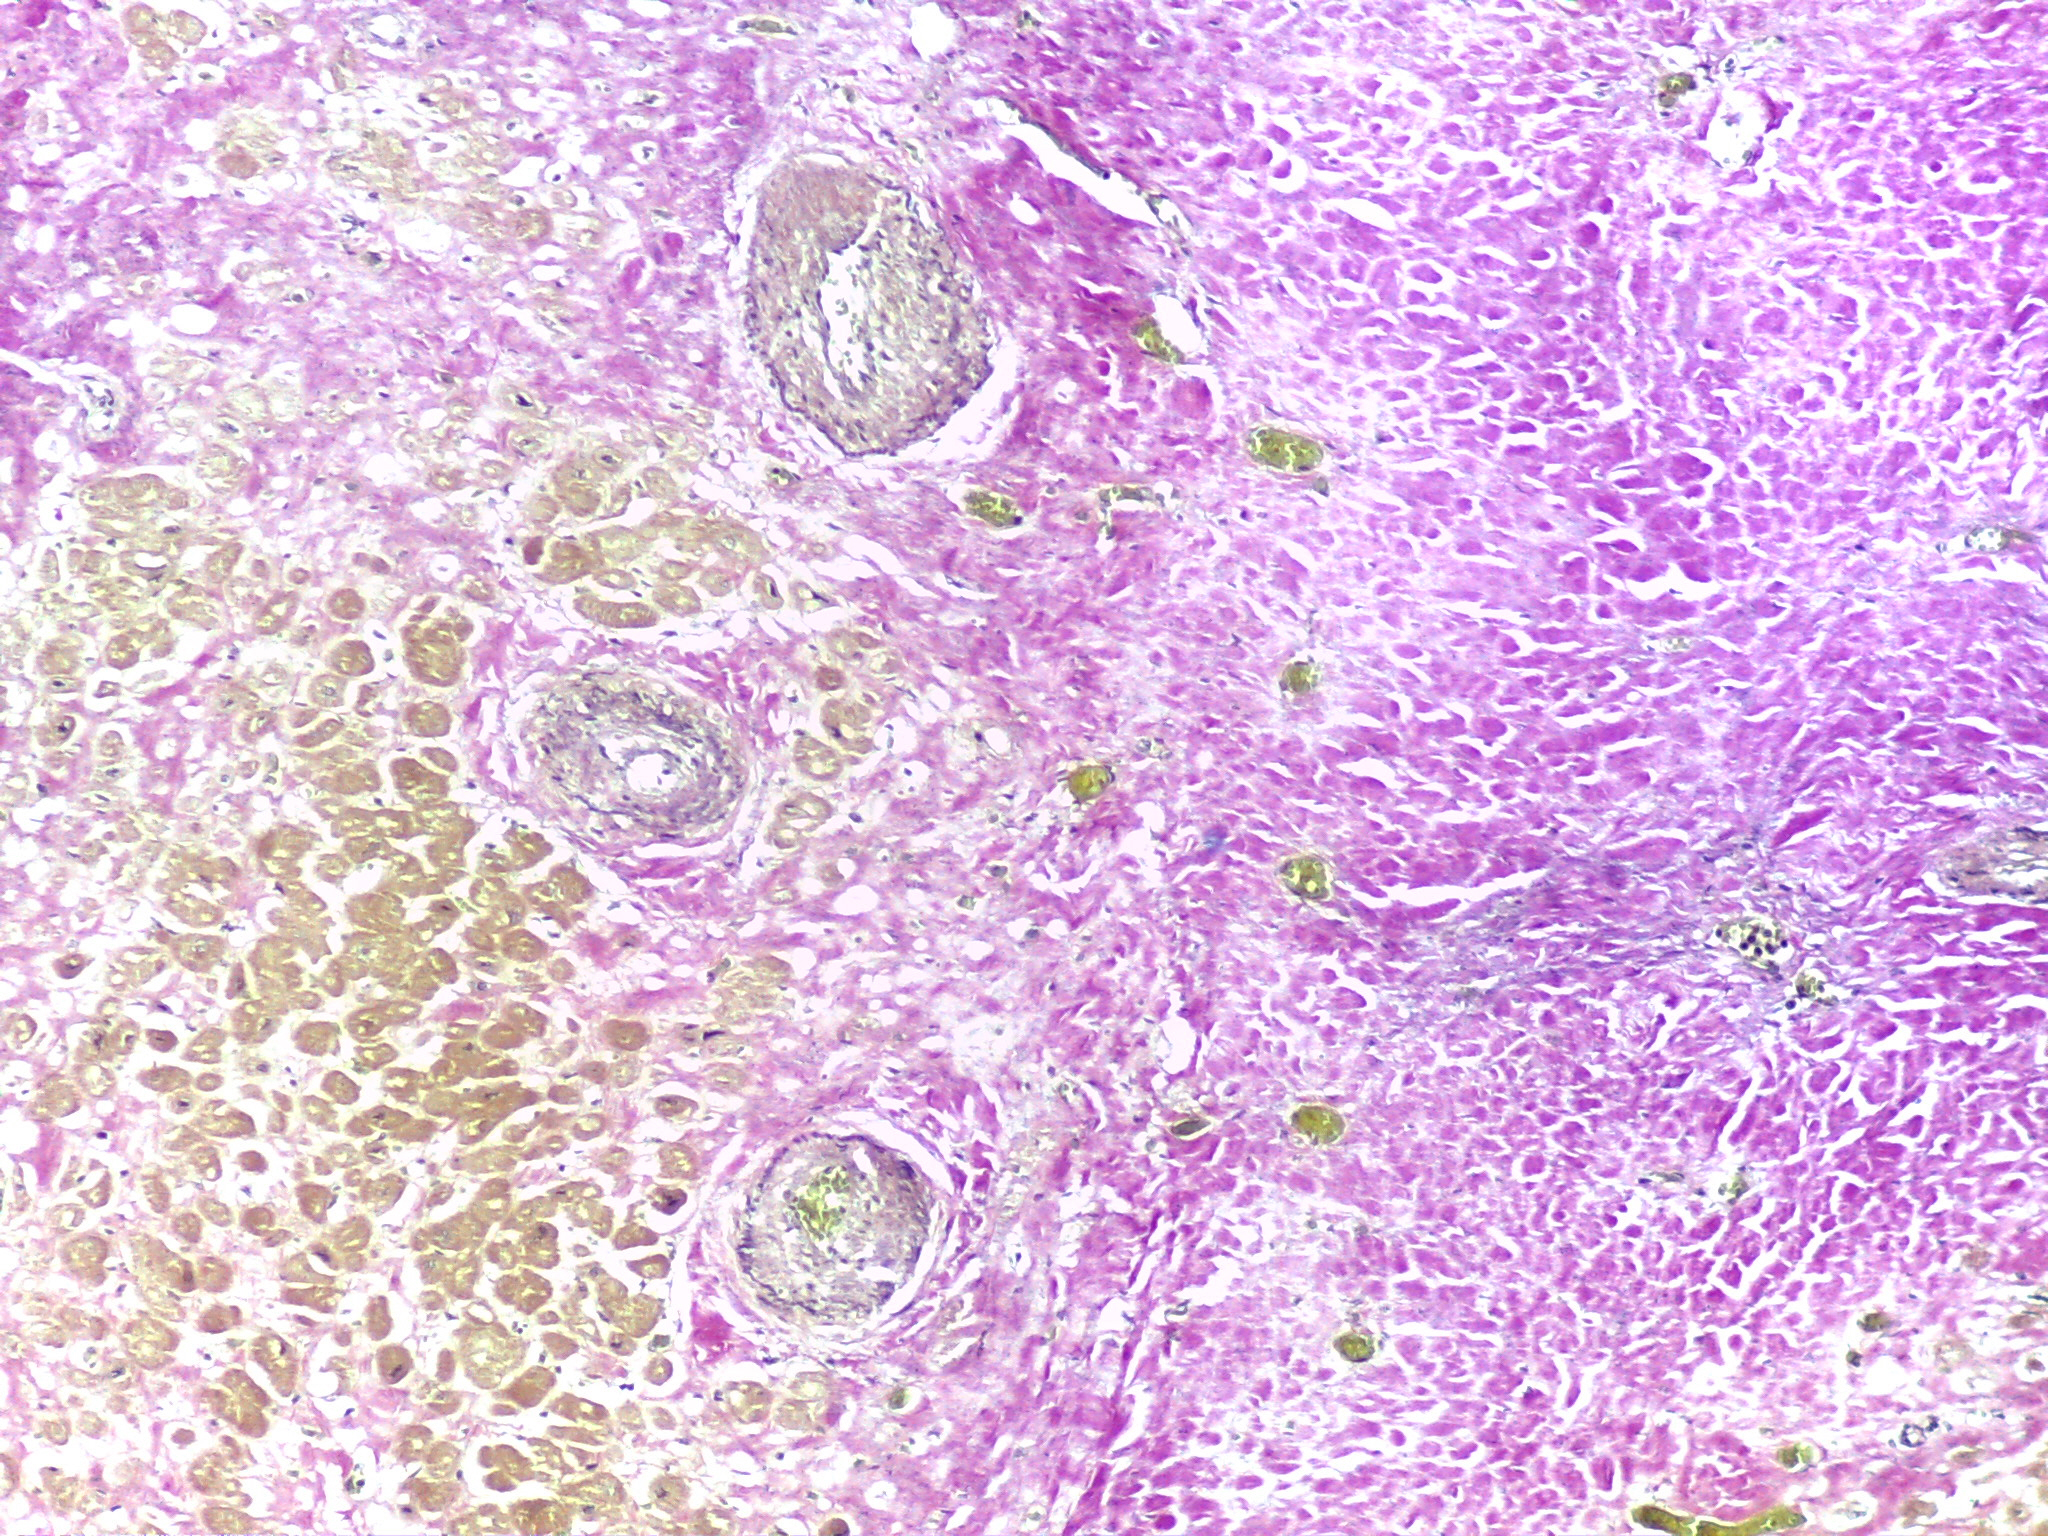

Figure 3. Area with thicken-walled arteries at the interface between the fibrous scar (right) and the adjacent myocardium (left) [EvG x100] (source: INMLCF, I.P.).